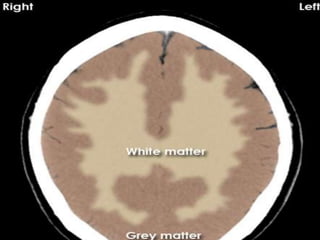

Grey and white matter differentiation

• Normally Grey matter is outer denser

structure and white matter in inner

hypodenser.

• Grey matter contains neurons cell bodies

while white matter contain axons with rich

fatty myelin sheath making it hypodense.

• This differentiation is loss in case of cerebral

odema.

Normal Grey white matter